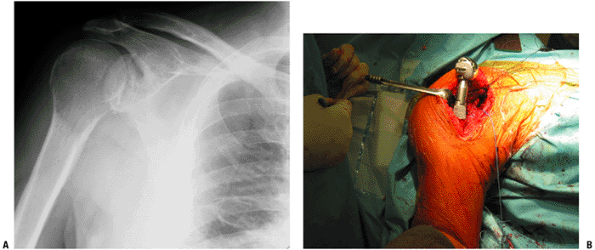

Scapula (Fig. 4.3-12)

Many patients with scapular bone sarcomas undergo

resection without reconstruction, but scapular endoprostheses are

available; proponents cite improved functional outcome through

lateralization of the shoulder joint.

Reconstructive options-

Flail shoulder reconstruction

-

Scapular endoprostheses (see Fig. 4.3-12)-

Need rhomboids, trapezius, latissimus dorsi, serratus anterior, some of rotator cuff